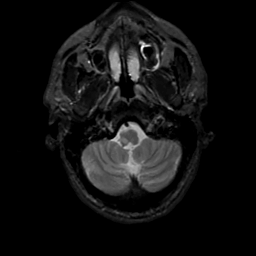

MR Study #4, March 3, 1991 -- Slice #6

[Home][Help][Clinical][Tour 1][Tour 2] Slice 6